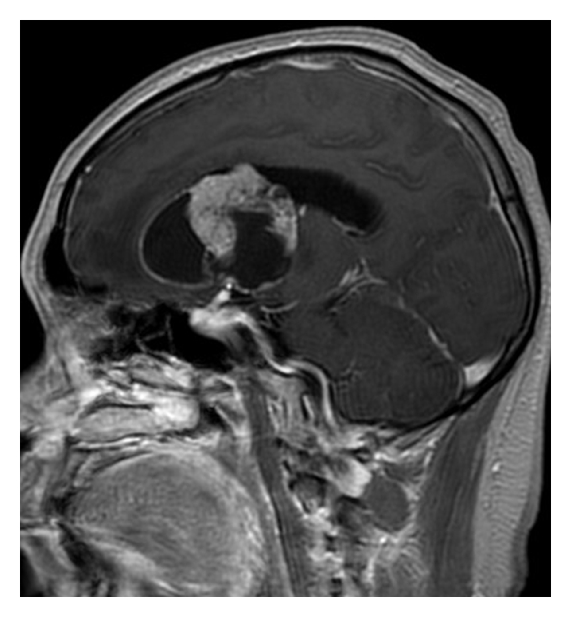

A 42-year-old Japanese man was admitted to our hospital for headache and nausea. These symptoms had progressed for 4 days before admission, and he was gradually unable to walk steadily. Magnetic resonance imaging (MRI) revealed a mass lesion with marked cyst components. The lesion had a maximum diameter of 58 mm (Figure 1). T1-weighted images (WIs) after gadolinium administration showed ring enhancement. T2WIs showed slight edema around the lesion. Proton magnetic resonance spectroscopy (1H-MRS) analysis of the nodule showed an increased ratio of choline to creatine and an apparent peak for lactate, which is strongly correlated with tumor malignancy. In contrast, the peak for N-acetylaspartate (NAA) was within the background noise level (Figure 2). The neuroimaging diagnosis was a primary malignant brain tumor such as glioblastoma multiforme (GBM) or a metastatic brain tumor. The patient underwent subtotal removal of the lesion via a fronto-temporal craniotomy.

(a)

(b)

(c)

(d)